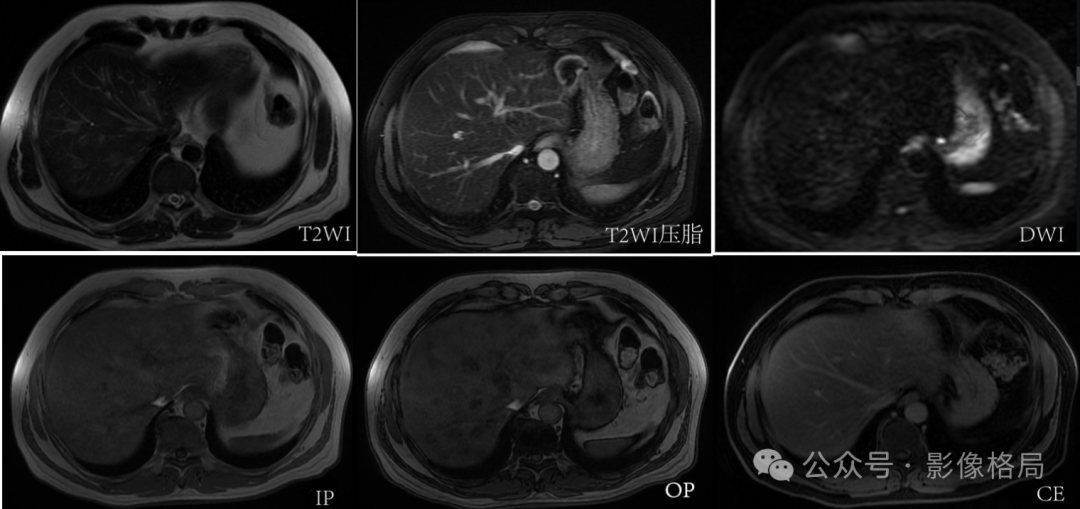

Case: A 48-year-old male, incidental finding of multiple focal liver lesions during a health check-up.

Multiple well-defined lesions in the liver parenchyma, high signal on T1 and T2, with reduced signal intensity on T2 fat-suppressed and out-of-phase sequences. No diffusion restriction on DWI/ADC sequences. No abnormal enhancement on contrast scans. — Multifocal hepatic steatosis.